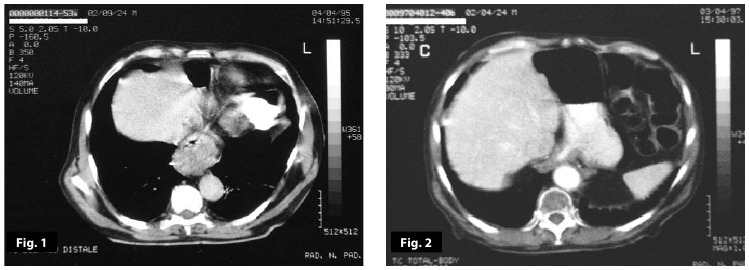

Figure2

Figure1-2

Figure1-2-3-4